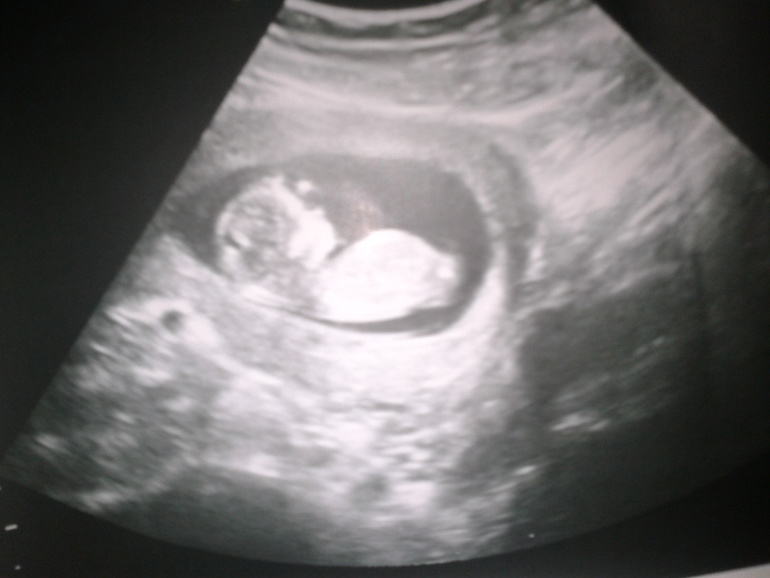

1 скрининг)

УЗИ, КТГ, доплерНу что,тайна остается тайной еще на месяц...ибо воооообще не ясно кто там)) цитирую "вроде что то торчит,но торчит не так,как должно торчать у мальчиков"

с одного ракурса вроде на девочку похоже,с другого,не очень..)))

в общем развиваемся по сроку, 5,5см КТР, никаких аномалий,отклонений нет)) все четко видно,и носик и подбородочек,и ручки и ножки,все все)) оно там дрыгается,шевелит всем чем можно, прыгает,танцует...кароче это будет шилопоп)))) СБ 156 уд. в мин. главное что все хо-ро-шо!

но он искренне недоумевает что у его дочки может торчать...а, еще была фраза "может пацан,но у него че то там примялось и теперь торчит не так?"